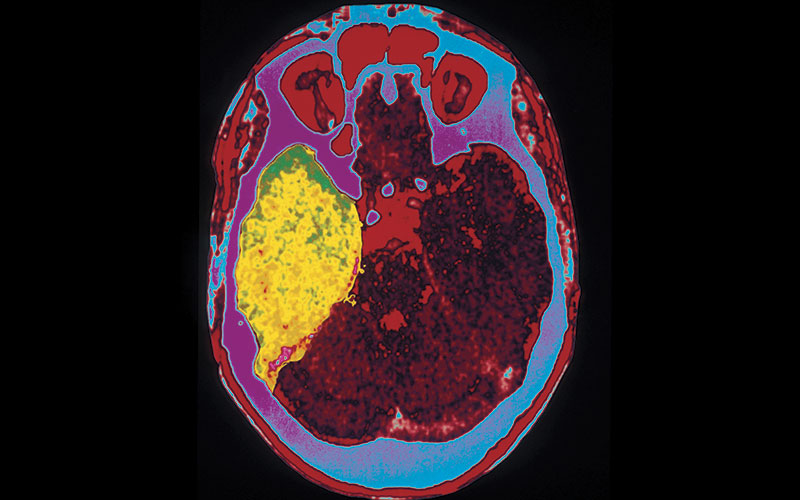

V tomto stádiu již může virus postihnout centrální nervový systém a dochází k rozvoji závažných onemocnění, jako jsou záněty mozku, mozkových blan či míchy.